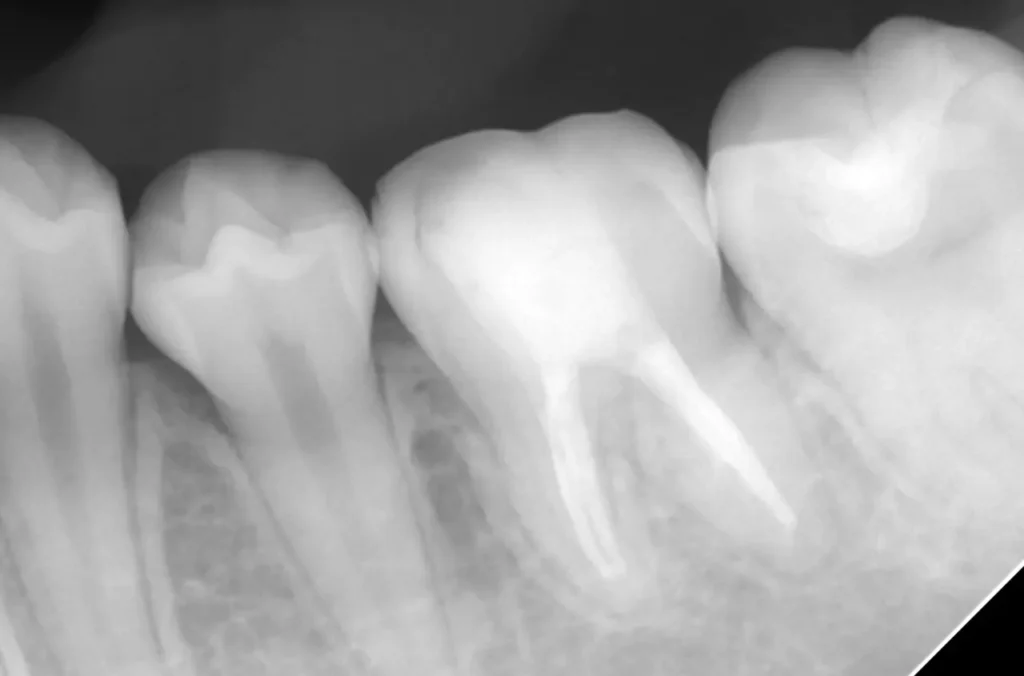

自費根管治療症例3 治療前

紹介元で半年間根の治療を受けているがうずく痛みがとれないので紹介されて受診

初診時

根の先が黒ずんで炎症があります

術中

症状も消え根の先まで清掃できました

術後

理想的に終了し土台も作製、被せ物は依頼元で行うことになりました

精密根管治療(自費根管治療)治療開始

精密根管治療(自費根管治療)、治療回数3回、治療期間約1ヶ月、治療費(大臼歯再治療)15万3千円+4,500円X3回  クラウン補綴処置は他院で継続治療

根の治療を専門的に行い、クラウンなどかぶせ物は他院で行うことも可能です。

治療後

症状はすべて改善、経過4年後

術後4年

症状もレントゲン上の炎症も全く再発はありません